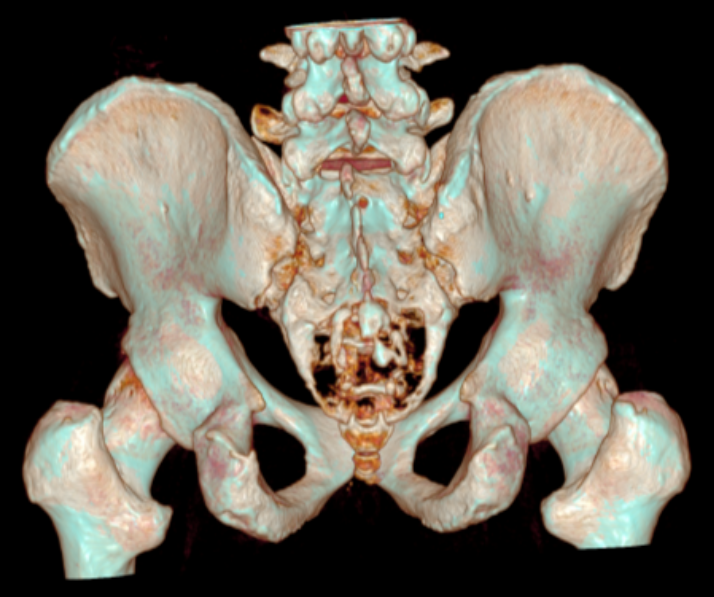

为预防术中意外情况,保证患者手术安全,赵波副教授、欧阳鹏荣主治医师在术前为患者进行骶尾骨及肿瘤的计算机三维重建、计算机模拟手术、3D模型打印,为患者制定了精密的手术方案。最终,由王栋教授主刀,在赵波副教授、欧阳鹏荣主治医师、李宇欢住院总医师配合下,在麻醉科李伟副主任、严百惠副教授、李亚护士的保驾护航下为患者成功进行了骶骨肿瘤切除术。在保留双侧骶2神经根的前提下,成功切除骶3及以下骶尾骨,并瘤外完整切除肿瘤,术中出血仅600ml,手术圆满完成,术后患者双下肢感觉运动良好。在脊柱与骨肿瘤病区赵辰护士的精心护理下,患者逐渐从手术创伤中恢复,腰臀部疼痛消失,大便恢复正常。最终病理检查诊断为脊索瘤,安排好后续治疗后,患者顺利步行出院。